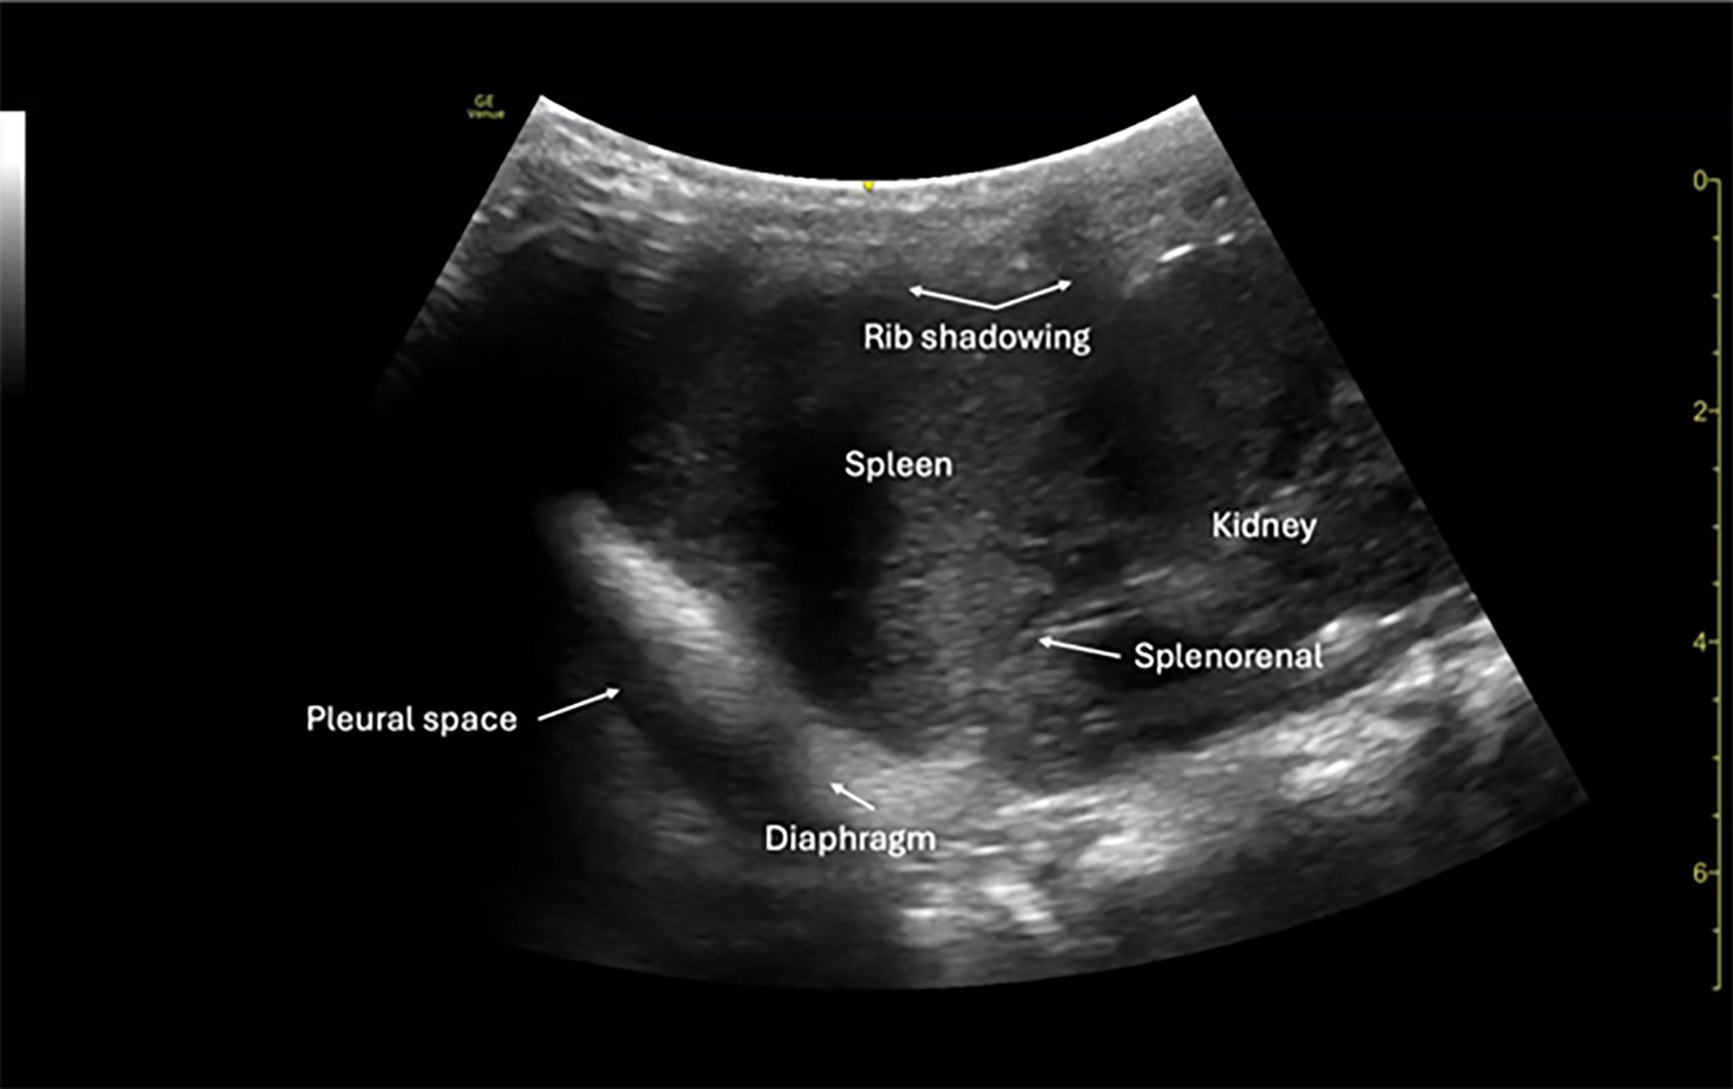

Left Upper Quadrant

The left upper quadrant (LUQ) view in the FAST exam is colloquially known as the “knuckles in the bed” view because of the often awkward probe position required to visualize the splenorenal recess, left pleural space, and inferior pole of the left kidney. This window can be technically challenging, especially in larger or uncooperative pediatric patients, because it typically requires the examiner to press deeply with the probe angled posteriorly beneath the rib cage. As such, the examiner’s hand or knuckles typically will push into the bed to achieve the appropriate window, hence its moniker. In children, the spleen is proportionally larger and more anteriorly positioned, which can facilitate acquisition of this view compared to adults.

The deepest space in the LUQ is the left subphrenic space, which underscores the importance of including the diaphragm in the field of view to detect intraperitoneal and pleural fluid. Anechoic fluid may collect between the spleen and diaphragm, spleen and kidney, or along the inferior pole of the spleen. Careful fanning through the coronal plane ensures adequate evaluation of these dependent spaces.

In pediatric patients, this view may demonstrate fluid tracking from the suprasplenic or splenorenal regions, although free fluid is less commonly isolated to the LUQ compared to the pelvis or RUQ.28 Still, when present, LUQ fluid is highly specific for significant injury and correlates most often with splenic injury, the most commonly injured solid organ in pediatric blunt abdominal trauma.39

Probe selection and technique are particularly important in this view. The curvilinear probe is standard, but a phased-array probe may be helpful in smaller patients or when rib spacing is limited. Gentle probe pressure is essential to avoid compression of underlying structures, and imaging in both longitudinal and transverse planes increases sensitivity.

While the LUQ view has a lower sensitivity in detecting isolated injuries when compared to the pelvic or RUQ windows, its inclusion remains critical, especially given the high incidence of splenic injuries in pediatric blunt trauma.31 In one study, the presence of LUQ free fluid was associated with a positive predictive value of 87% for intra-abdominal injury requiring intervention.29 (See Figure 2.)

Figure 2. Normal FAST Left Upper Quadrant |

5-year-old female via curvilinear probe |

FAST: Focused Assessment with Sonography for Trauma Image courtesy of: Matthew D. Holmes, MD. |